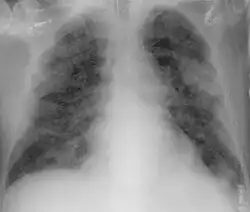

From the CT scans of COVID-19 infected lungs, white patches were observed containing fluid known as ground-glass opacity (GGO) or simply ground glass.[130] This tended to correlate with the clear jelly liquid found in lung autopsies of people who died of COVID-19. One possibility addressed in medical research is that hyuralonic acid (HA) could be the leading factor for this observation of the clear jelly liquid found in the lungs, in what could be hyuralonic storm, in conjunction with cytokine storm.[131]

Imaging

Chest CT scans may be helpful to diagnose COVID‑19 in individuals with a high clinical suspicion of infection but are not recommended for routine screening.[175][187] Bilateral multilobar ground-glass opacities with a peripheral, asymmetric, and posterior distribution are common in early infection.[175][188] Subpleural dominance, crazy paving (lobular septal thickening with variable alveolar filling), and consolidation may appear as the disease progresses.[175][189] Characteristic imaging features on chest radiographs and computed tomography (CT) of people who are symptomatic include asymmetric peripheral ground-glass opacities without pleural effusions.[190]

Many groups have created COVID‑19 datasets that include imagery such as the Italian Radiological Society which has compiled an international online database of imaging findings for confirmed cases.[191] Due to overlap with other infections such as adenovirus, imaging without confirmation by rRT-PCR is of limited specificity in identifying COVID‑19.[190] A large study in China compared chest CT results to PCR and demonstrated that though imaging is less specific for the infection, it is faster and more sensitive.[174]